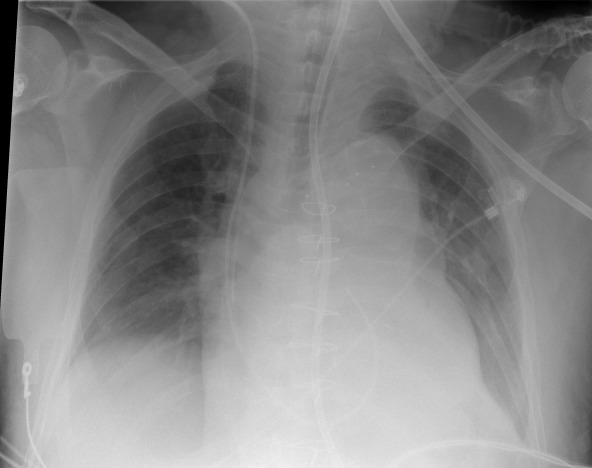

Attaching and de-attaching a grid in urgent care situations adds time and physical effort to the imaging process. This slows the path to diagnosis and increases the chance of error through potential issues like grid misalignment. Gridless X-ray capabilities provide a solution to this challenge, but come with their own set of complications such as an increased likelihood of scattered radiation that negatively impacts image quality.

SkyFlow gridless X-ray reduces the effect of scattered radiation for non-grid bedside chest exams, allowing for DR images with grid-like contrast while avoiding the time and effort of attaching and detaching a grid. SkyFlow identifies scatter signal and automatically applies correction immediately at the bedside, allowing radiologists to review images and make decisions on the spot.

With no grid to attach, SkyFlow scatter correction algorithm achieves the high-image contrasts that lead to a confident clinical diagnosis in emergency settings.